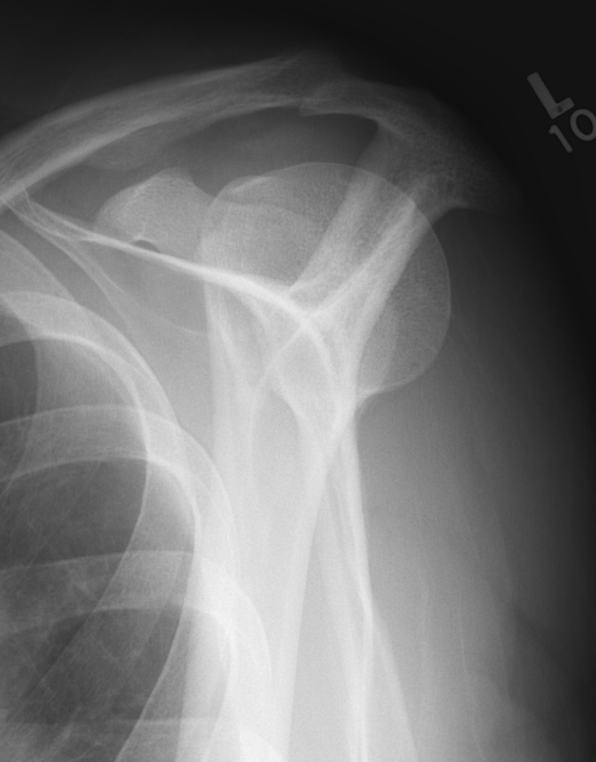

Posterior shoulder dislocation

Posterior shoulder dislocations

Scapular lateral

Center of the humeral head must be centered on the Y / Mercedes sign

Y is formed by

- coracoid anteriorly

- scapular spine posteriorly

- scapula body inferiorly